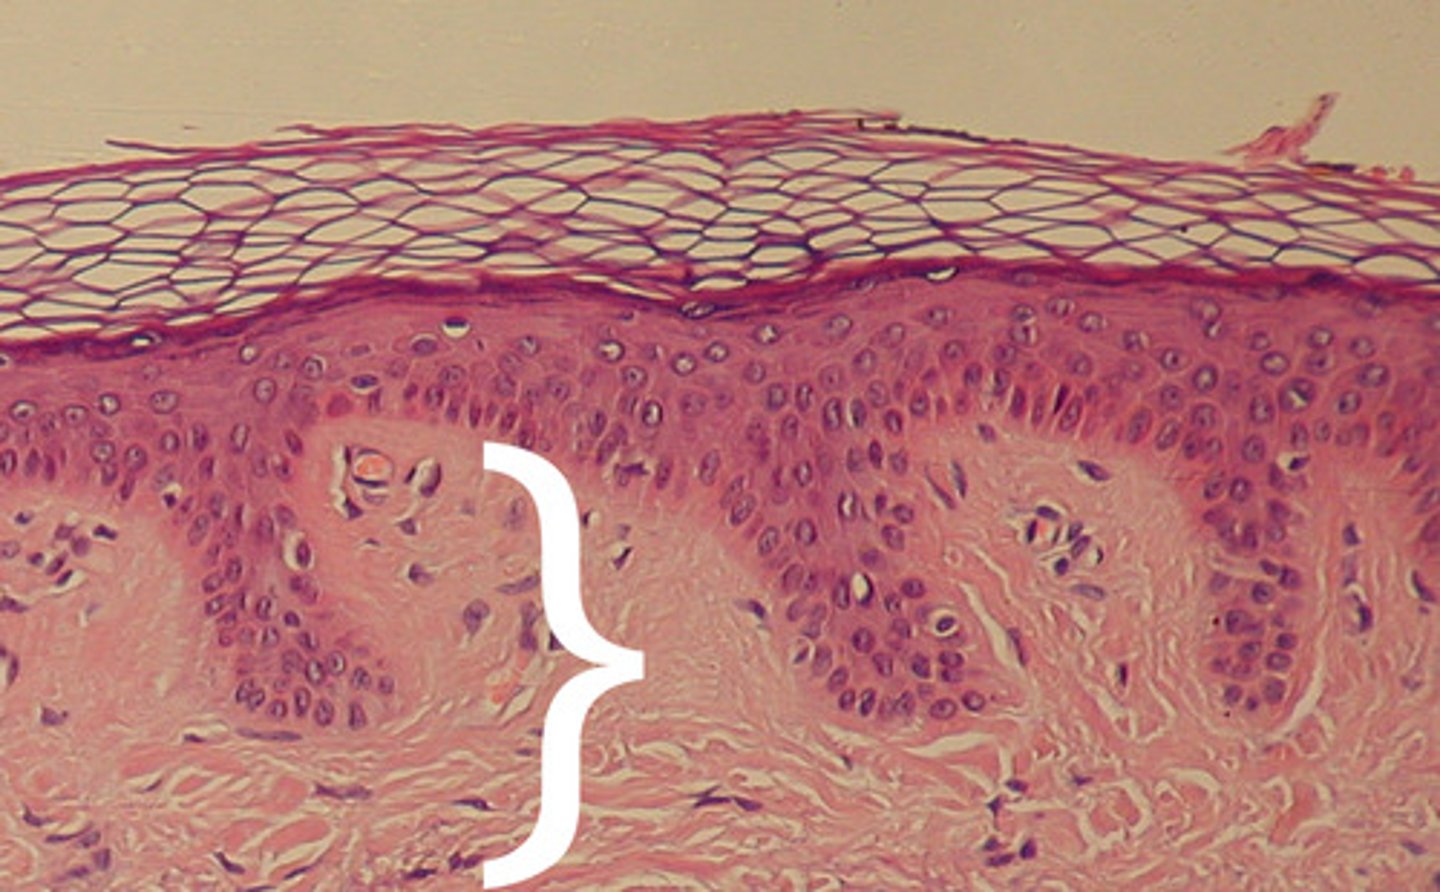

Epidermis

Outer layer of skin

stratum corneum

outermost layer of epidermis

stratum lucidum

Clear, transparent layer of the epidermis under the stratum corneum.

stratum granulosum

a layer of the epidermis that marks the transition between the deeper, metabolically active strata and the dead cells of the more superficial strata

stratum spinosum

stratum basale

the deepest layer of the epidermis consisting of stem cells capable of undergoing cell division to form new cells

Dermis

Inner layer of skin

papillary layer

outer layer of the dermis, directly beneath the epidermis; made of loose connective tissue

reticular layer

The deeper layer of the dermis that supplies the skin with oxygen and nutrients; made of dense irregular connective tissue

dermal papillae

a fingerlike projection of the dermis that may contain blood capillaries or Meissner corpuscles (of touch)